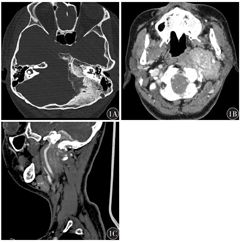

影像学检查:CT检查示左侧后颅窝骨质密度增高,内板呈毛刷状改变,累及左侧颞骨乳突部及岩部、枕骨大孔及斜坡。左侧后颅窝底、邻近颈静脉孔区及左侧咽旁间隙颈动脉鞘可见明显强化肿块影,其内可见钙化,肿物自后颅窝经颈静脉孔向颈部蔓延,左侧颈内动脉颈段被包绕其中并向外前方移位,邻近颈内静脉显示不清,左侧颈静脉孔增宽,左侧内听道变窄,左侧鼻咽、口咽腔变窄,左侧茎突受压推挤向前外侧移位。左侧鼓膜稍增厚,鼓室内软组织密度影(图1)。增强磁共振成像(MRI)示左侧咽旁间隙及颈动脉间隙可见团块状明显强化影,信号均匀,边界尚清,大小约6.0 cm×5.2 cm×3.6 cm,病变包绕左侧颈内动脉颅外段、颈内静脉,并沿左侧颈静脉孔、左侧舌下神经管与颅内左侧桥小脑角池区同类病变相延续,相应颅底孔道略扩大并充满强化影,左侧面听神经被包绕,邻近硬膜轻度增厚强化并延续至椎管内。病变周围左侧颞骨、枕骨增生硬化,局部见膨胀性骨质压迫吸收,左侧茎突受压移位。病变周围左侧腮腺及左侧颈后肌群前外侧缘受压改变,左侧头长肌、咽黏膜间隙受压前移,咽鼓管显示不清,脑实质未见明显异常强化(图2)。综合影像学结果后诊断为沟通性MEP。